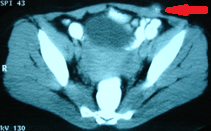

CT. Σημαντικό αιμάτωμα εκτεινόμενο στον προκυστικό χώρο (Ευγενική παραχώρηση Dr. V. Penopoulos).